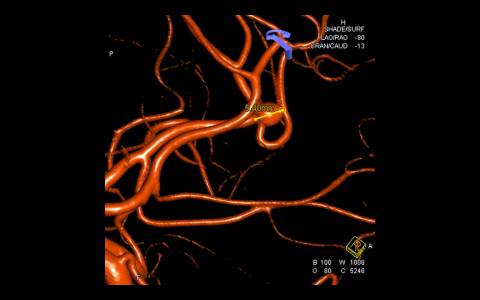

Realizado angiografia cerebral e reconstrução 3D sendo evidenciado um aneurisma de colo largo com ramo frontal emergindo do colo do aneurisma. Baseado nessas característica, foi optado por tratamento com stent redirecionado de fluxo Fred Jr., associado a micromolas de platina devido o importante inflow do ramo frontal.

Implantado um stent 2,5 x 18mm conforme programação 3D. O procedimento transcorreu sem intercorrência, mantendo a patência dos vasos envolvidos.